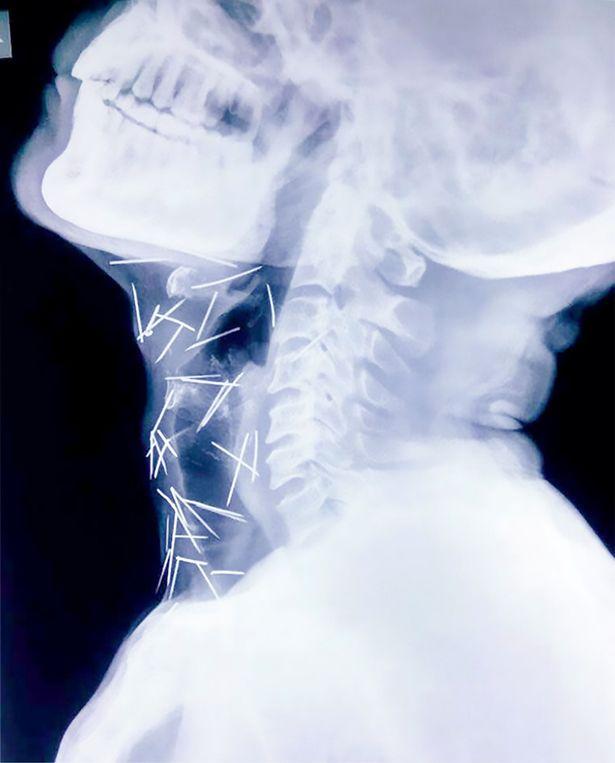

Asta nu a fost tot. Noi radiografii au arătat că bărbatul avea ace și în gât. 40 la număr, așa că a fost din nou suspus unei intervenții chirurgicale, scrie Mirror.

În total, 75 de ace cu gămălie au găsit medicii. Bărbatul susține că nu știe cum au ajuns acestea în corpul său, însă doctorii cred că acestea au fost înghițite voluntar.